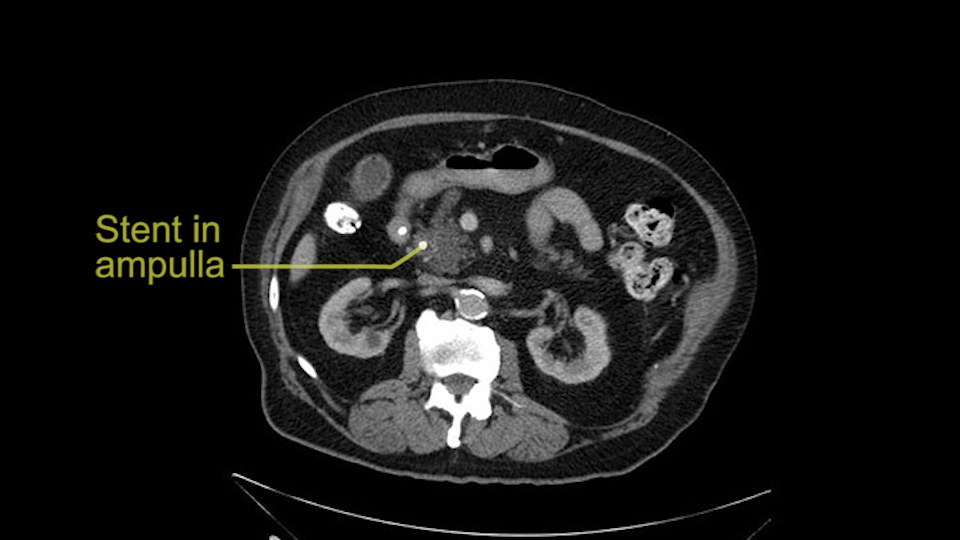

The other thing I look at is the gastroepeiploic arcade- which is this thing here- which is where the gastroepeiploic vein joins the portal vein. I call it the gateway to the neck of the pancreas because you pretty much have to divide it to get to the neck. The middle colic vein usually drains either into it or nearby. I think we’re seeing it here. Again,that can be divided and I usually divide those two and it helps me get under the neck. Again, there’s no issues here with the tumor so it’s nice from that perspective. If I was concerned about the vein, which I’m not here, I would go to the coronal view. It’s a nice way to look at the vein on just a couple of cuts and you can see a beautiful view of it here. There’s the portal vein, there’s the head of the pancreas. There’s the tumor. It’s a little closer here than it looks on the other one. I doubt it’s involved. If it’s touching, it may not be invading it but even if it was, it's a short segment. Anyways, there’s the SMV there’s the splenic vein, and everything looks good. You can see the stent. I ignore the stent. It’s the most dramatic looking thing in the picture but it’s actually the least important.

The patient that is being discussed just now is an 83-year old gentleman with obstructive jaundice with a biopsy-proven ampullary cancer, adenocarcinoma with very raised and high levels of bilirubin. What has been presented to me has been an axial and coronal images of the CT scan prior to the stenting 3 months ago. It’s a periampullary tumor as per the CT scan assessment that I have done. And then the CT scans have been repeated again. The patient did undergo an ERCP with what I suppose is a plastic stent and not a self-expandable metal stent.